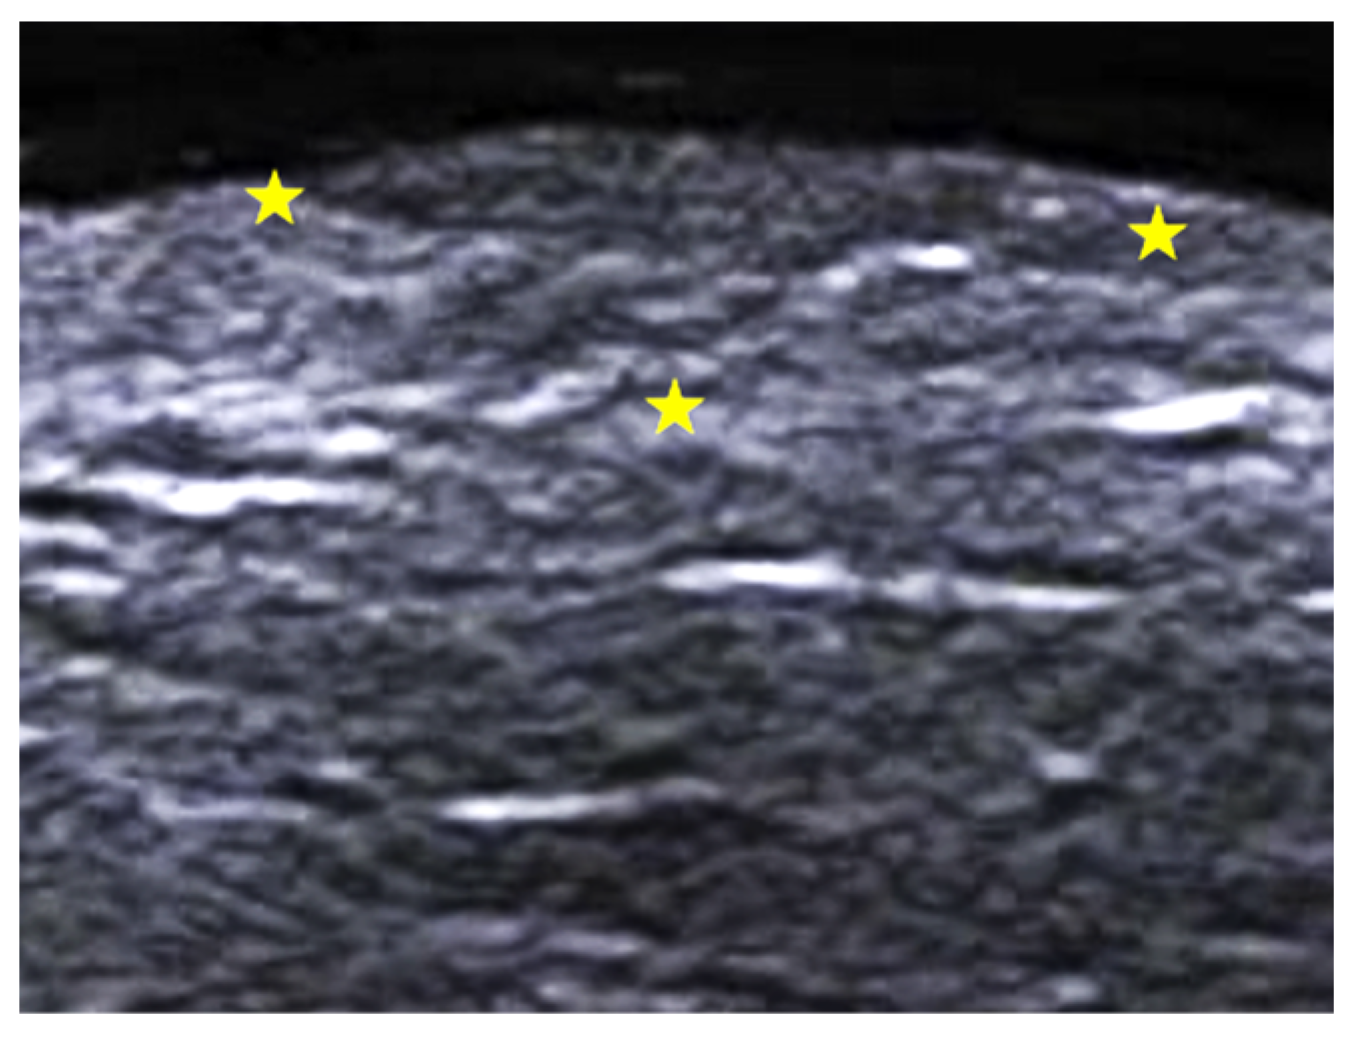

2. Infections